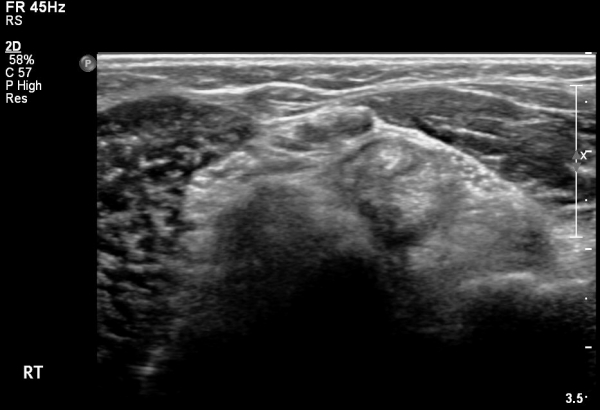

Á¶±Ý´õ ¸»´ÜÀ¸·Î À̵¿ÇÏ´Ï °ÇÀÌ °üÂûµÇÁö ¾ÊÀ½(»çÁø 3).